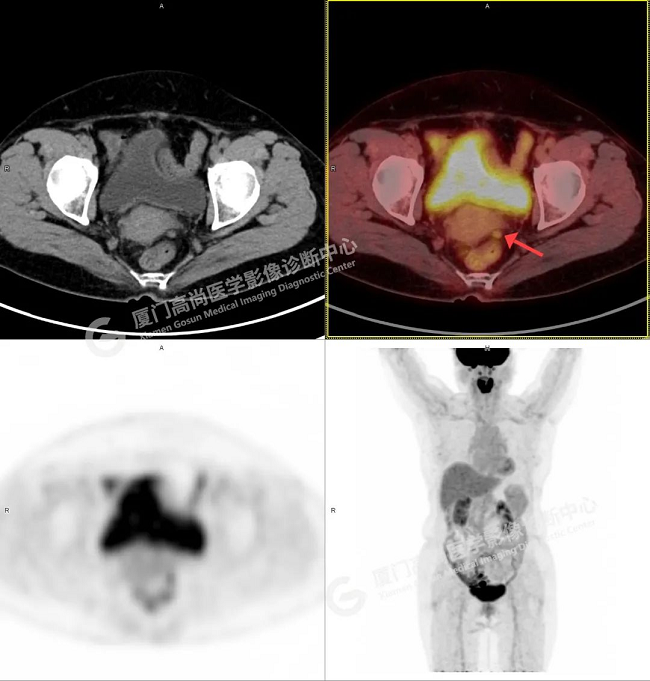

初步診斷:右側附件區(qū)囊實性占位伴腫大淋巴結,考慮卵巢來源惡性腫瘤,卵巢Ca可能性大。為進一步明確病灶良惡性、大小、是否有轉移,吳阿姨在我中心進行了PET/CT檢查。

PET/CT影像圖

診斷意見:1、右側附件區(qū)囊實性結節(jié),代謝增高,考慮為卵巢來源惡性腫瘤(囊腺癌)

2、子宮直腸陷凹內多發(fā)腫大淋巴結,代謝不同程度增高,考慮為轉移。

術后病理顯示:卵巢高級別漿液性癌2期。